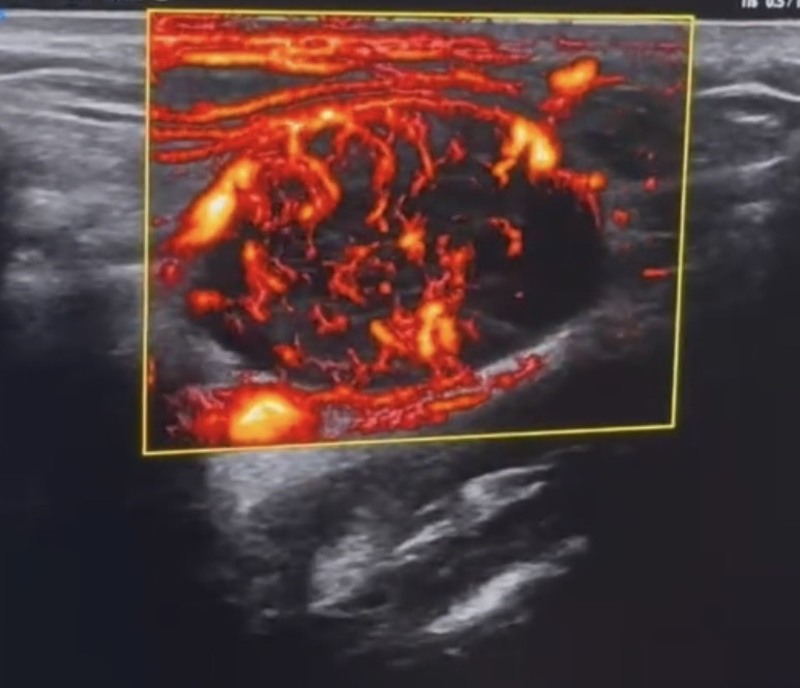

Đặc điểm siêu âm Doppler

- Mạch máu phân bố rốn hạch

- Trở kháng thấp

- Siêu âm:Vùng góc hàm bên trái ghi nhận vài cấu trúc hạch echo kém xen lẫn dải echo dày không đồng nhất, mất rốn, bờ đều kích thước từ 26-32mm, dạng bầu dục, mạch máu phân bố ngoại vi lẫn trung tâm.